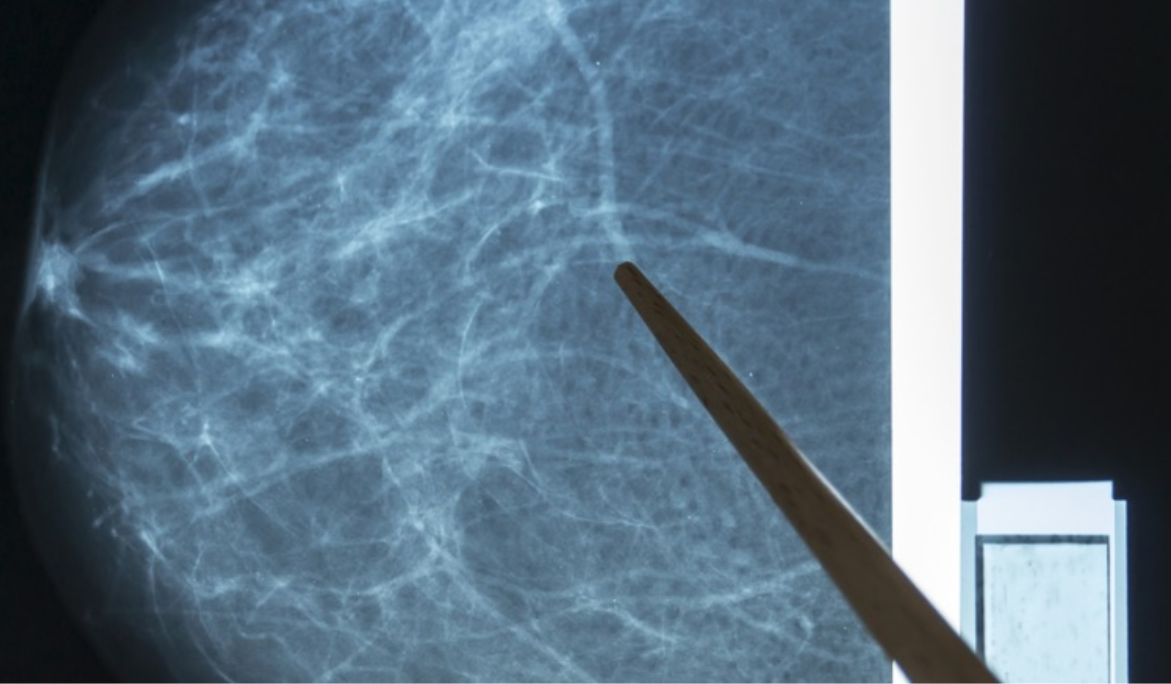

Los sistemas de detección asistida por computadora (CAD) utilizan una imagen mamográfica digitalizada que puede obtenerse de una mastografía de película convencional o de una mamografía adquirida digitalmente. El software de la computadora busca áreas anormales de densidad, masa o calcificación que pueden indicar la presencia de cáncer. El sistema CAD resalta estas áreas en las imágenes, alertando al radiólogo sobre la necesidad de análisis adicionales. La mastografía sigue siendo el estándar de oro para la detección del cáncer de seno en etapa temprana. El objetivo de la mastografía es la detección temprana del cáncer de seno, a través de la detección de masas y / o microcalcificaciones (pueden aparecer pequeños trozos de calcio dentro de los tejidos blandos del seno).

En mujeres con tejido mamario fibroquístico denso, la masa mamaria se muestra blanca en una mastografía; los tumores también son blancos. Con las mastografías digitales, el radiólogo puede manipular el contraste de las imágenes, haciéndolas más oscuras o más claras, lo que permite identificar las masas. Las imágenes también se pueden ampliar en la computadora para enfocarse en áreas de alerta.